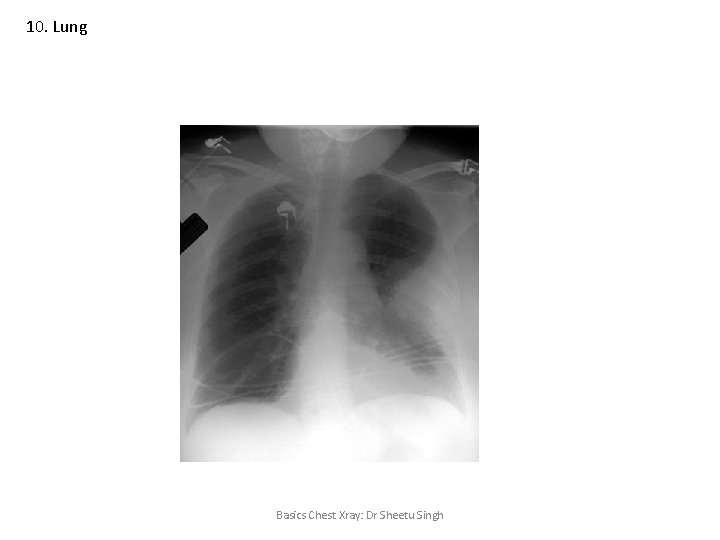

10. Lung Basics Chest Xray: Dr Sheetu Singh